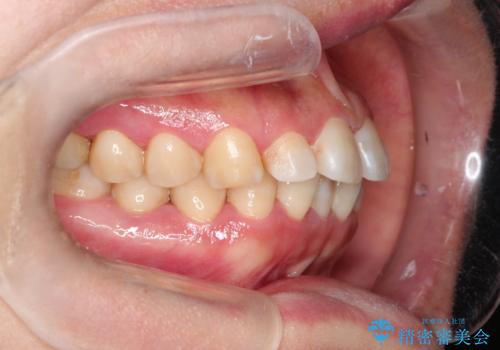

【インビザライン】前歯のすきまを閉じたい

- 前歯の隙間を主訴に来院されました。

インビザライン にて治療を行い、歯並びを改善することができました。